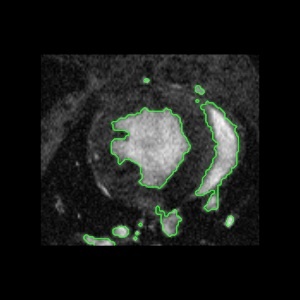

An Insight Toolkit (ITK) processing framework for simultaneous segmentation of multiple objects using active contours without edges is presented in this paper. These techniques are also popularly referred to as multiphase methods. Earlier, we had an implemented the Chan and Vese [1] algorithm that uses level- sets to accomplish region segmentation in images with poor or no gradient information. The current work extends that submission to use multiple level sets that evolve concurrently. The basic idea is to partion the image into several sets of piecewise constant intensity regions. This work is in contrast to the level-set methods currently available in ITK which necessarily require gradient information and also necessarily segment a single object-of-interest. Similar to those methods, the methods presented in this paper are also made efficient using a sparse implementation strategy that solves the contour evolution PDE at the level-set boundary. This work does not introduce any new filter but extends the earlier submitted to filters to process multiple objects. We include 2D/3D example code, parameter settings and show the results generated on a 2D cardiac image.